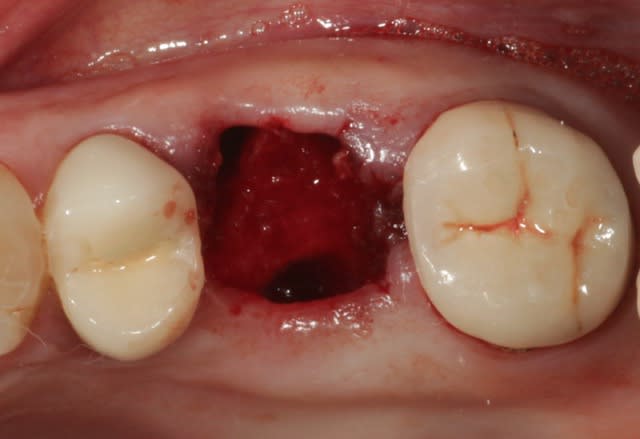

16 extraite, soulevé de la membrane sinusienne au piezo et pose d'un implant dans la foulée, comblement de l'alvéole au Bio-Oss.